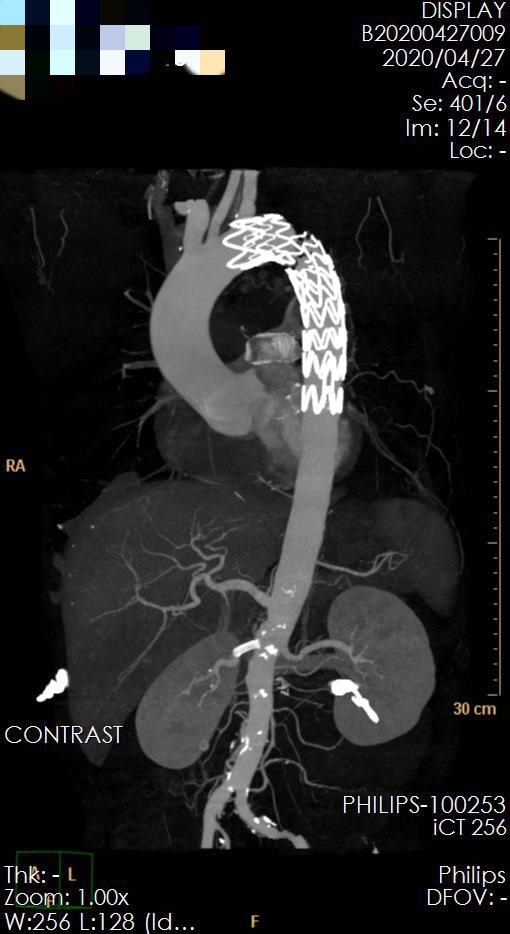

来到医院后王兵教授及崔文军主任给他制定了详细的治疗计划,血压高压达到180mmHg,赶紧用药降压,口服加静脉联合降压,结果四种口服降压药联合,血压还得大剂量的静脉降压药物才能控制。等待急性期过后,安排做了个微创手术,采取胸主动脉覆膜支架腔内隔绝术,为了改善血压水平,防止右肾萎缩、失去功能,右侧肾动脉放置了一枚支架,手术非常顺利。术后经调理后血压心率很快稳定,降压药逐渐减量,病人顺利康复。

▲ 图3 术后复查,胸主动脉支架位置良好,右肾动脉血流通畅良好,肾动脉显影双侧无差异